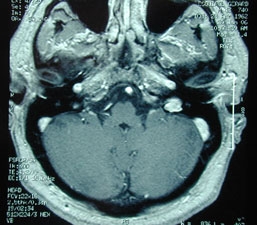

L’oreille moyenne doit être explorée avec nos moyens spécifiques, microscope, optique rigide, reliés à des systèmes de capture d’images.

Nous disposons de tous les moyens d’exploration et de traitement chirurgical des pathologies de l’oreille.